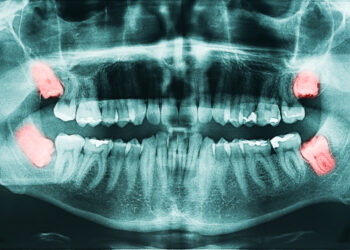

Skaityti daugiauDetailsPerikoronitas yra būklė, kai dantenos aplink protinius dantis (kitaip – trečiuosius krūminius) pradeda tinti ir užsidega. Šie dantys dažniausiai išdygsta...